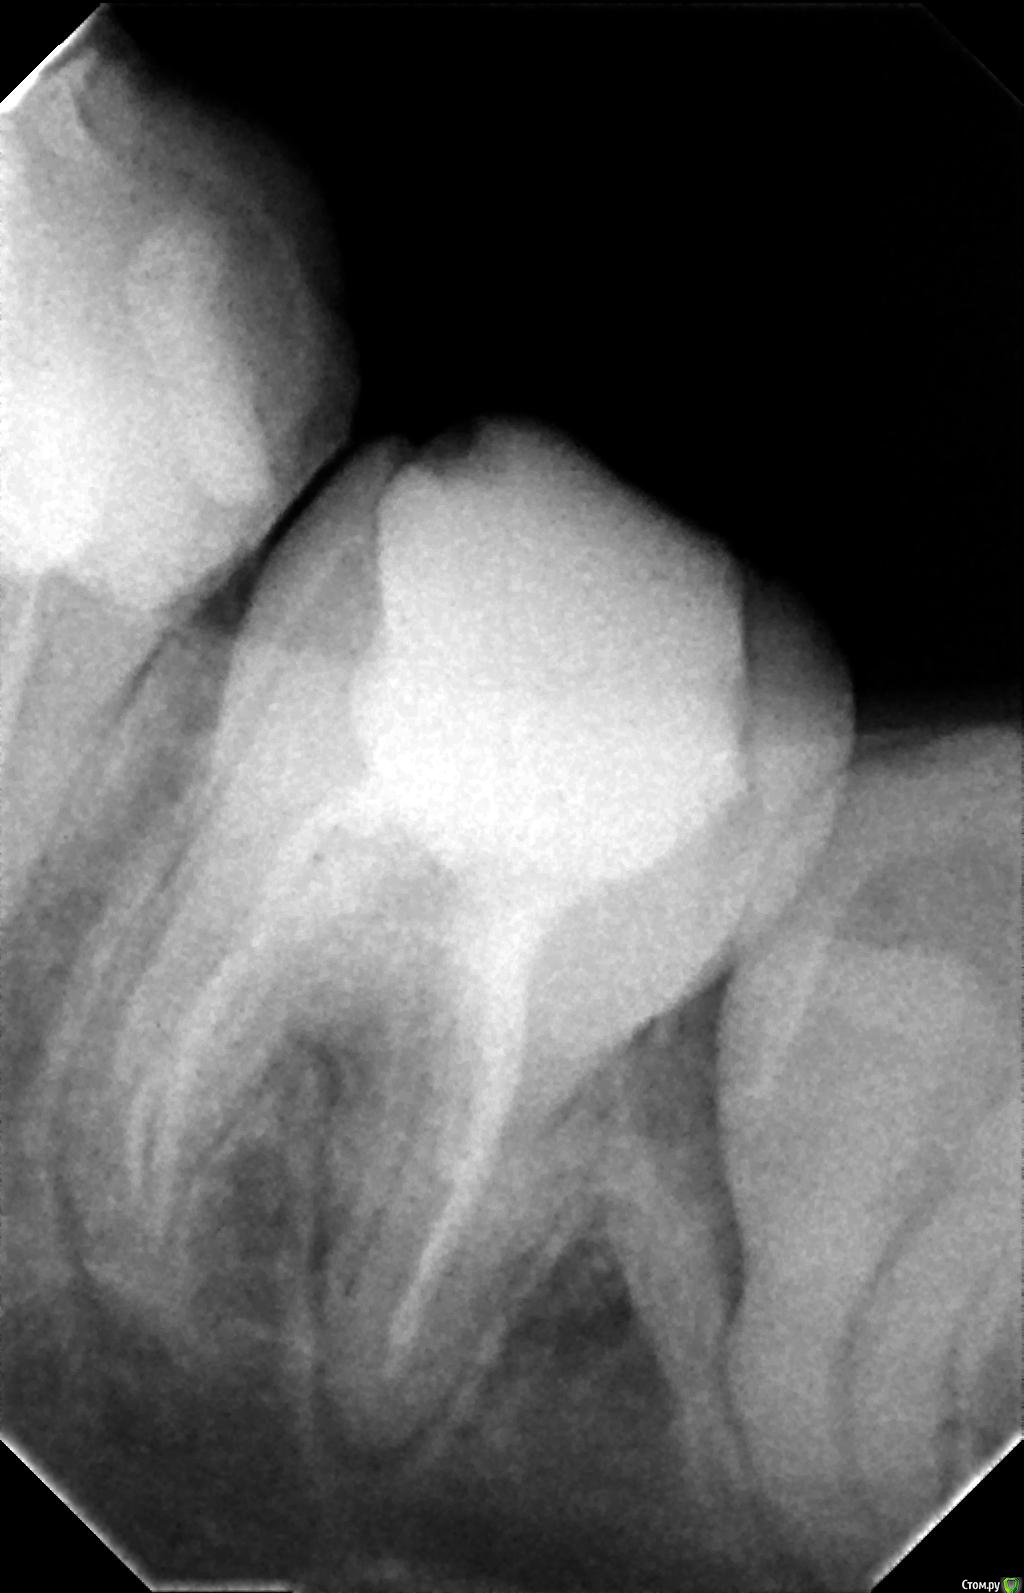

Ёлкаа Опубликовано 8 февраля, 2016 Поделиться Опубликовано 8 февраля, 2016 Добрый день!Помогите, пожалуйста, совсем не знаю, что мне делать.На "мертвом" зубе образовалась киста. В основном врачи рекомендуют удалить зуб.Подскажите, пожалуйста, есть ли возможность сохранить зуб или в этом нет смысла. Фото 5-ки, 6-ки и 7-ки прилагаю.Также в дальнейшем в планах ставить брекеты.Помогите, я совсем запуталась Заранее спасибо! Ссылка на комментарий

red_butler Опубликовано 8 февраля, 2016 Поделиться Опубликовано 8 февраля, 2016 Если судить только по снимкам, то лечить. Очный осмотр расставит все по местам. 1 Ссылка на комментарий

DmitrySH Опубликовано 8 февраля, 2016 Поделиться Опубликовано 8 февраля, 2016 Конечно лечить!Ничего очень страшного на снимках не вижу и в большинстве случаев такие зубы успешно сохраняются. Ссылка на комментарий